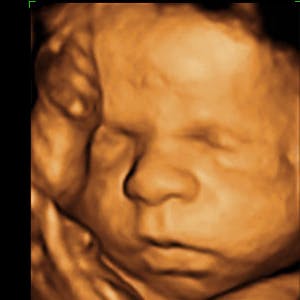

Gravid

Vi gør en dyd ud af at klæde dig godt på både før, under og efter din graviditet. Vi ved, at der kan komme mange spørgsmål til din graviditet, fødsel, amning, din babys udvikling og mange flere emner, derfor har vi samlet guides, tips & tricks samt læsernes egne fortællinger i dette gravid univers.